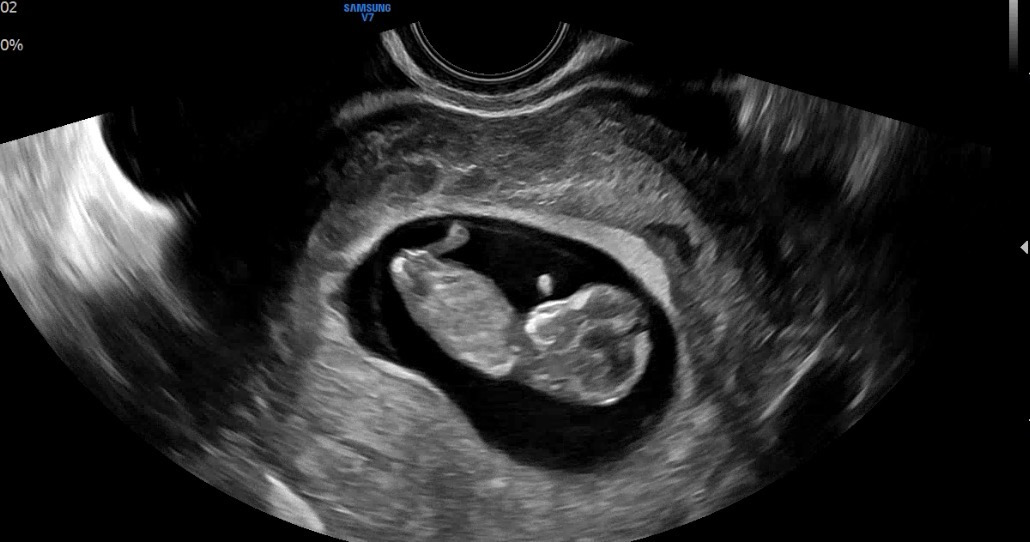

안녕하세요 :) 10주 2일차인데 아직 이르긴 하지만 각도법으로 성별 유추 될까요~?

아니요! 생식기 발달이 12주 전후라 10주는 너무 일러요!